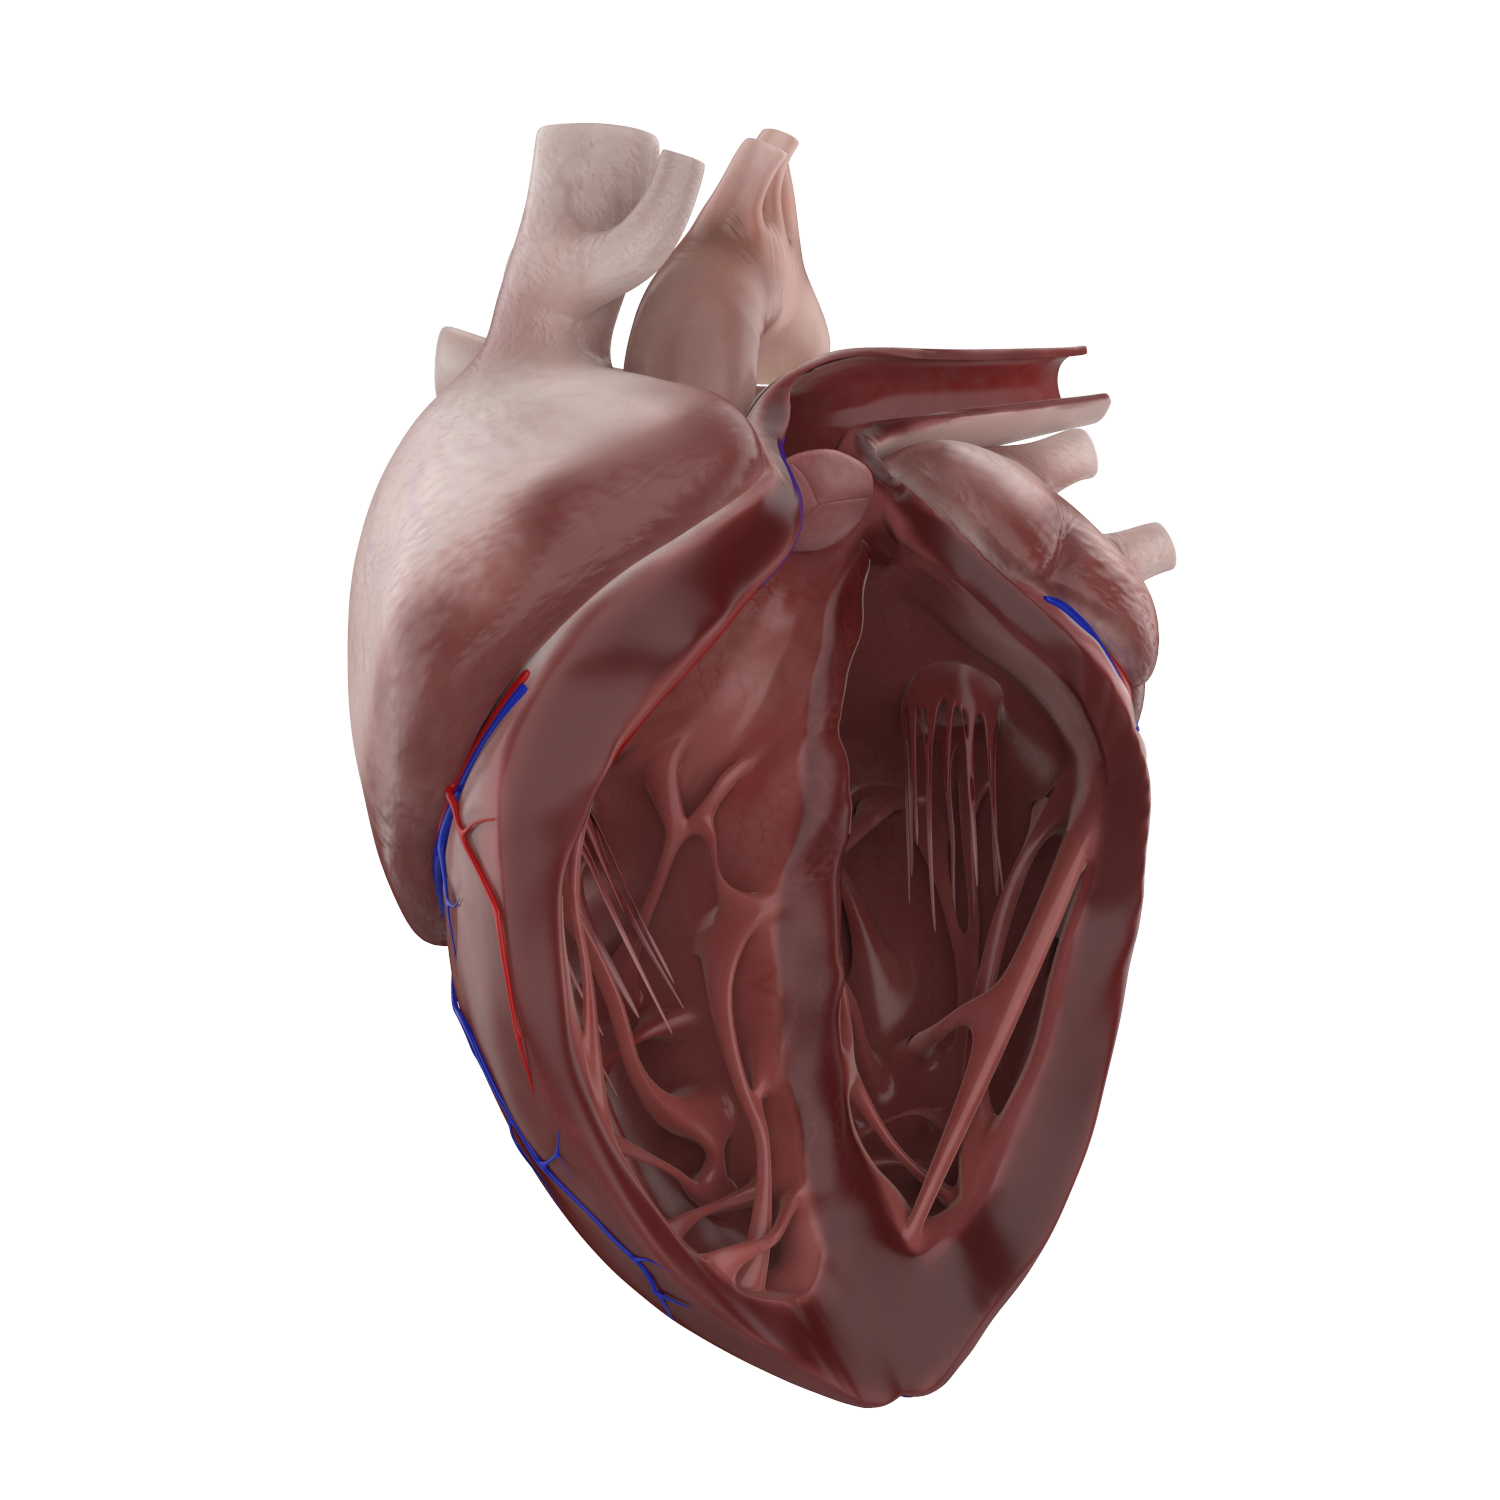

Human Heart Drawing Outline at GetDrawings | Free download  3d anatomy human heart

3d anatomy human heart  Show me a diagram of the human heart? Here are a bunch! - Interactive Biology, with Leslie Samuel

Animated Realistic Human Heart - Medically 3D asset  Zygote::3D Heart Model | Medically Accurate | Human Anatomy

Zygote::3D Heart Model | Medically Accurate | Human Anatomy  Zygote::Solid 3D Human Heart Model

Zygote::Solid 3D Human Heart Model  3D human heart anatomy model - TurboSquid 1283134

3D human heart anatomy model - TurboSquid 1283134  anatomy human heart 3d c4d

anatomy human heart 3d c4d  Modeled human heart section 3D model - TurboSquid 1657004

Modeled human heart section 3D model - TurboSquid 1657004  Heart by Rustamova on @DeviantArt | Anatomical heart art, Anatomy art, Heart drawing

Human Heart Section 3D model | CGTrader  human heart - internal anatomy 3d model

human heart - internal anatomy 3d model  3D Illustration Human Heart 3D Images - Iwish Iwas

3D dissected human heart model - TurboSquid 1361664  10 Realistic Heart Drawings and Tattoos â Simple Human Heart Sketch for 2022 | Do It Before Me

Human Heart Section 3D model | CGTrader  3d human heart

Human Heart Cutaway Anatomy 3D model section | CGTrader  Human Heart by Mutantenmaid on DeviantArt

human heart interior 3d model  Image of Human Heart 3D Illustration | Stock Image MXI28575

Human Heart Anatomy 1 3D model | CGTrader  human heart anatomy 3d max

3d model heart anatomy  3d human heart anatomy model

3d human heart anatomy model  3d human heart section

3d human heart section  human heart solidworks 3d model

human heart - internal anatomy 3d model  Heart Diagram Human Heart Images Hd 3D - img-Badr